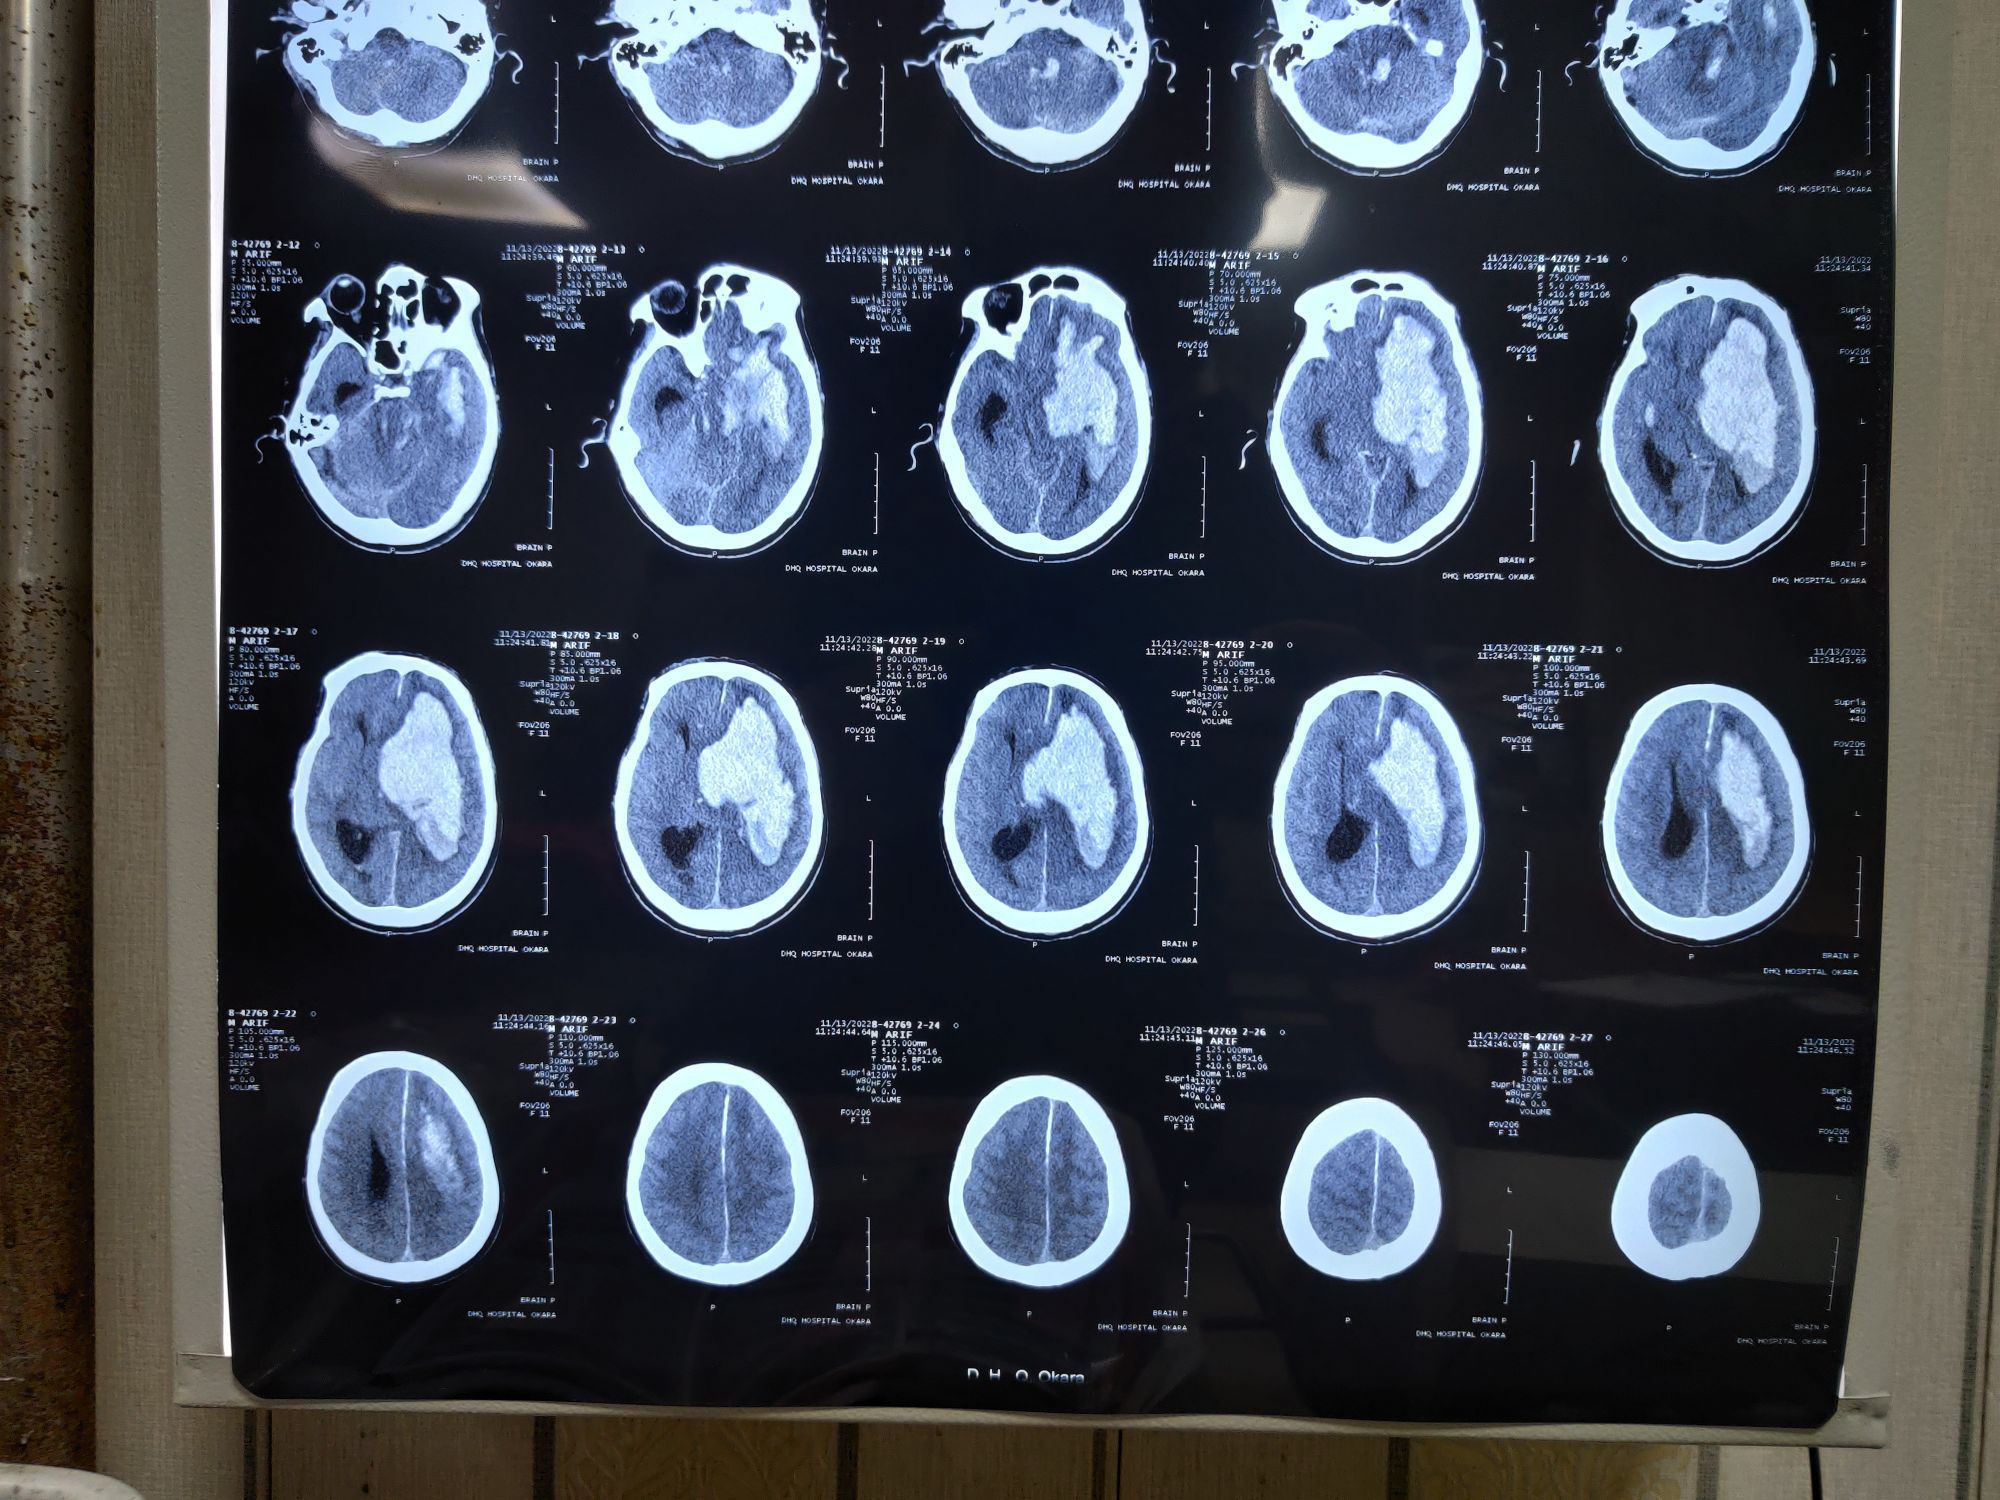

Massive hemorrhagic CVA

Er

Cva

Hypertensive